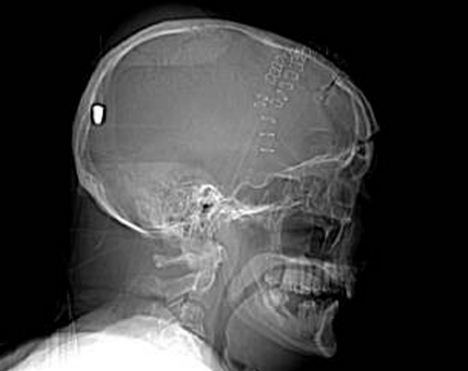

CT掃描顯示子彈留在彼得老人的腦部

據(jù)英國(guó)《每日郵報(bào)》5月11日?qǐng)?bào)道,英國(guó)一名61歲的老人上個(gè)月19日在花園干活時(shí)被一顆流彈擊中腦部竟奇跡存活,目前他半身癱瘓但無(wú)生命危險(xiǎn)。5月10日,警方為了破案公布了彼得先生的腦部掃描圖片,希望知情者提供相關(guān)線索。

事情的經(jīng)過(guò)是這樣的,彼得在整理花園的時(shí)候突然摔倒在地不省人事,他的家人還以為他中風(fēng)了,但醫(yī)院對(duì)其大腦掃描后卻發(fā)現(xiàn)了令人驚悚的事實(shí):一顆子彈不知由于何種原因從左眼窩進(jìn)入他的大腦,并深深植入其腦后部。但不可思議的是彼得竟然活了下來(lái),雖然身體部分癱瘓且失去了語(yǔ)言和記憶能力。

負(fù)責(zé)調(diào)查此案的警官史蒂夫表示:“這可能是我調(diào)查過(guò)的最詭異的一個(gè)案子了?!苯?jīng)過(guò)對(duì)掃描圖片的鑒定,警方彈道專(zhuān)家賈爾斯認(rèn)為這顆子彈很像是從一種通常用于射殺兔子的.22口徑獵槍里射出的。

“如果在10碼外開(kāi)這種槍?zhuān)訌棔?huì)穿透彼得的腦部,但若是從800到1000碼以外,子彈會(huì)失去大部分的沖擊力,只能穿透軟組織。所以說(shuō),在這個(gè)距離內(nèi),子彈若射中彼得腦殼會(huì)被彈回,不可能進(jìn)入腦中,”賈爾斯說(shuō)。